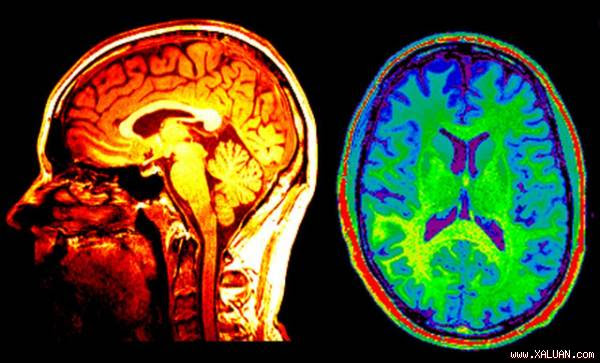

ảnh minh họa